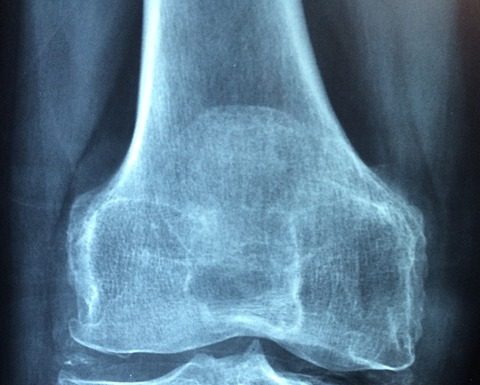

Reumatyzm to choroba, którą najczęściej kojarzymy z osobami w podeszłym wieku. Ponad siedemdziesiąt procent chorych stanowią kobiety, z powodu reumatyzmu mamy dodatkową jedną trzecią emerytur.

Wyleczenie choroby jest praktycznie niemożliwe, jednak poprzez jej szybkie rozpoznanie można sobie zaoszczędzić ogromnego bólu i niewygody w codziennym funkcjonowaniu. Jakie więc są objawy reumatyzmu?

Najbardziej znanym objawem reumatyzmu jest nieustanny ból. Dokucza nam szyja, plecy,...